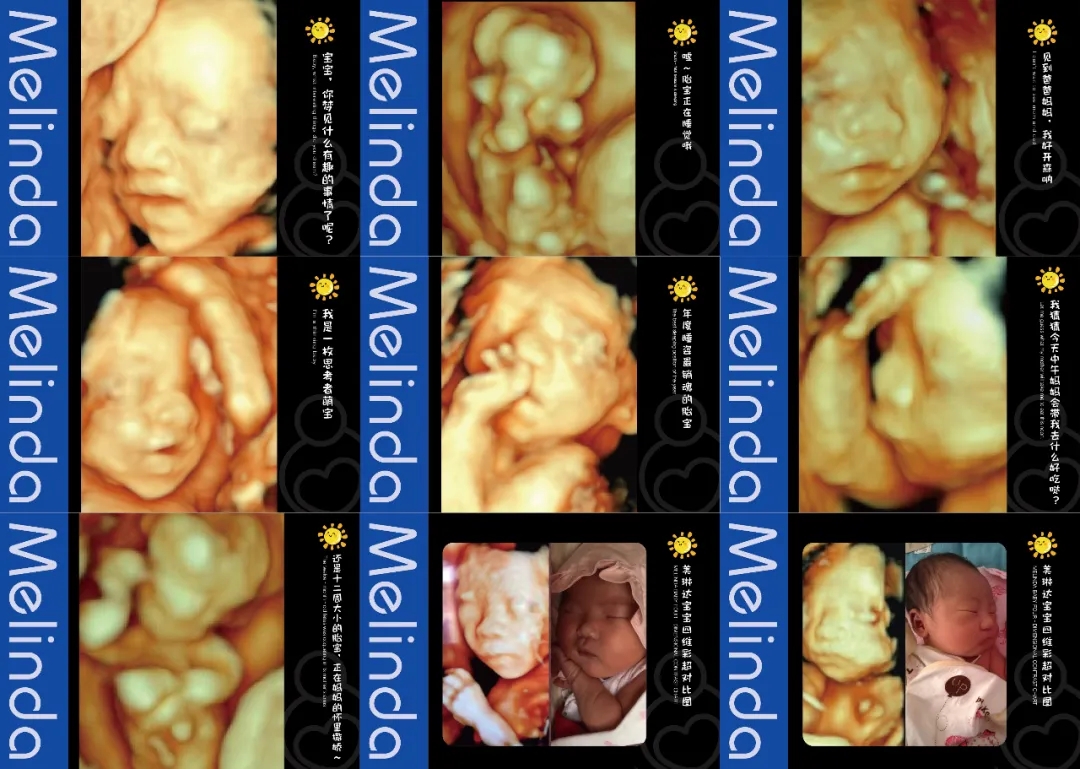

(美琳达四维宝宝照片)

(明星主播东玥两次四维检查胎宝照片对比)